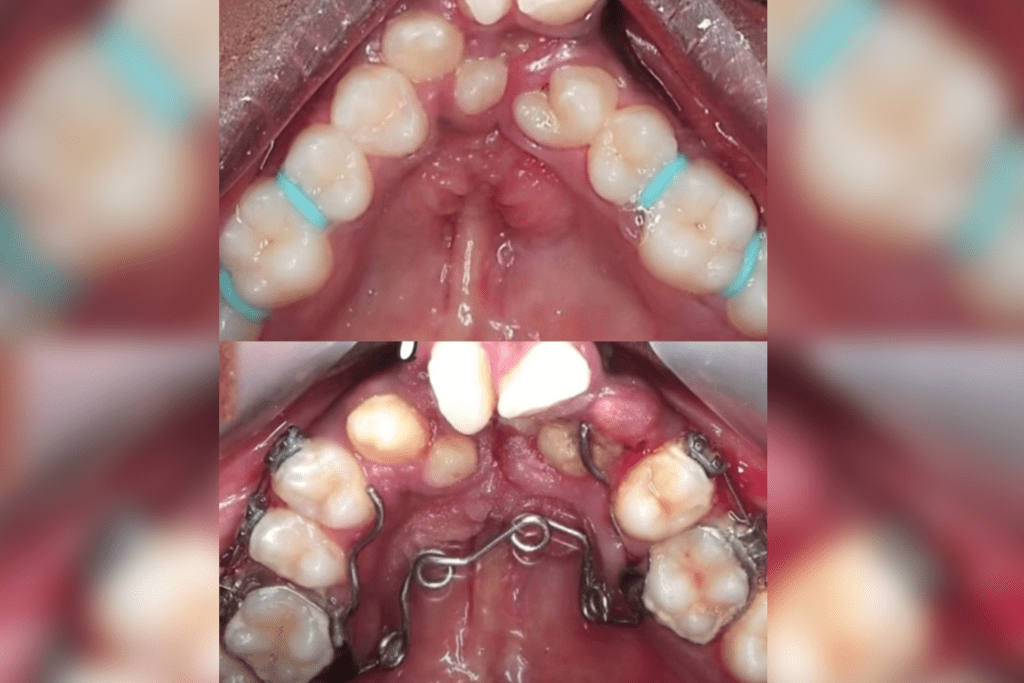

The lingual braces grab your teeth from the inside and, with the help of orthodontic wires, they move the teeth to their desired place.